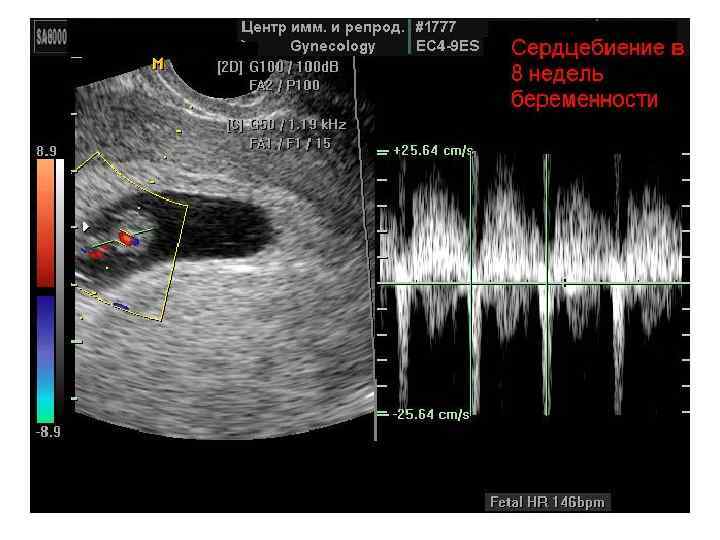

Скрининговое ультразвуковое обследование беременных Приказу Минздрава РФ № 457 от 28 декабря 2000 г. • 10 -14 недели беременности • 20 -24 недели беременности • 32 -34 недели беременности

Скрининговое ультразвуковое обследование беременных Приказу Минздрава РФ № 457 от 28 декабря 2000 г. • 10 -14 недели беременности • 20 -24 недели беременности • 32 -34 недели беременности

Определение сроков беременности при УЗИ (!? ) • Результат УЗИ полученный • в первом триместре (первые 12 недель беременности) позволяет вычислить срок родов с точностью 1 -3 дня, • во втором триместре (от 13 до 28 недель) ошибка увеличивается до 7 дней, • а после 28 недель (III триместр) очень сложно судить о сроке беременности по ультразвуковому размеру малыша.

Определение сроков беременности при УЗИ (!? ) • Результат УЗИ полученный • в первом триместре (первые 12 недель беременности) позволяет вычислить срок родов с точностью 1 -3 дня, • во втором триместре (от 13 до 28 недель) ошибка увеличивается до 7 дней, • а после 28 недель (III триместр) очень сложно судить о сроке беременности по ультразвуковому размеру малыша.